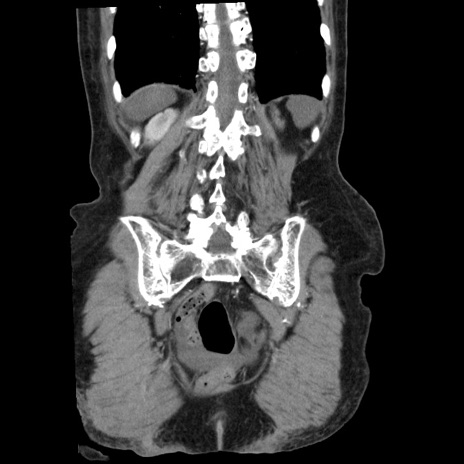

症例1(冠状断像)

症例

【症例】80歳代女性

【主訴】腹痛

【現病歴】8時間前から腹痛あり来院。

【既往歴】糖尿病、脂質異常症、子宮体癌にて子宮全摘術

【身体所見】意識清明・会話良好だが腹痛で苦悶様、全腹部にわたって反跳痛と圧痛あり

【データ】WBC 13600、CRP 0.14、LDH 224、CK 90